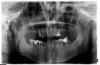

Д.С. Опубликовано 22 августа, 2009 Поделиться Опубликовано 22 августа, 2009 Здравствуйте!У меня на верхней челюсти осталось всего 6 передних зубов. Чтобы установить протез необходимо сточить по 2 зуба с каждой стороны, а я их даже не разу не лечила, т.е. они живые и здоровые, очень не хочется их портить, но по причине пародонтита говорят, что имплантация противопоказана.Посоветуйте пожалуйста что делать в таком случае. Покажите панорамный снимок Ссылка на комментарий

riana2 Опубликовано 22 августа, 2009 Автор Поделиться Опубликовано 22 августа, 2009 Покажите панорамный снимокНадеюсь, что получилось Ссылка на комментарий

Bier Опубликовано 23 августа, 2009 Поделиться Опубликовано 23 августа, 2009 я бы однозначно удалил 24, 37, 46 (?) 47(?)пародонтологическое лечение и имплантация. Ссылка на комментарий

Doc Опубликовано 23 августа, 2009 Поделиться Опубликовано 23 августа, 2009 я бы однозначно удалил 24, 37, 46 (?) 47(?)пародонтологическое лечение и имплантация. Аналогично! Эти сразу, остальные вроде послужат, но окончательный приговор только после осмотра и ощупывания. Я не поняла, этот снимок мне делали в стоматологической клинике, я его скопировала с диска, больше у меня ничего нет. Я должна записаться на ортопантограмму еще раз или у них в клинике как-то сохраняются мои снимки справа и слева. Обычно в клиниках все сохраняется. Ничего заново делать не придется. Ссылка на комментарий

doktor KID Опубликовано 25 августа, 2009 Поделиться Опубликовано 25 августа, 2009 Мое партфолио готово, такая "красавица" получилась.Два крайних зуба подлежат удалению, а куда остальные денутся, хотелось бы сохранить.Пожалуйста объясните подробнее какая предварительная подготовка требуется, какие импланты надо использовать в моем случае, что такое бюгель и куда лучше обращаться в Санкт-Петербурге.Верхний 4-й слева убирайте смело,на верхней челюсти это все!Двух сторонний синус лифтинги реставрация кости в области удаленного зуба,затем, если пройдет успешно,через 3-4 мес.операция имплантации(штрауман,реплейс или фриадент).Еще через 12 недель протезирование.И,собственно,красота!На н.ч.если есть подвижность крайних зубов и боли-удаление и имплантация,если нет можно отсрочить.Но это рано или поздно случиться,вам решать когда.Успеха вам! Да,если вам предложат поставить имплант сразу после удаления,это архи опасно! Ссылка на комментарий

riana2 Опубликовано 1 сентября, 2009 Автор Поделиться Опубликовано 1 сентября, 2009 Верхний 4-й слева убирайте смело,на верхней челюсти это все!Двух сторонний синус лифтинги реставрация кости в области удаленного зуба,затем, если пройдет успешно,через 3-4 мес.операция имплантации(штрауман,реплейс или фриадент).Еще через 12 недель протезирование.И,собственно,красота!На н.ч.если есть подвижность крайних зубов и боли-удаление и имплантация,если нет можно отсрочить.Но это рано или поздно случиться,вам решать когда.Успеха вам! Да,если вам предложат поставить имплант сразу после удаления,это архи опасно! Спасибо за столь подробные ответы и Ваше участие.Хотелось бы узнать Ваше мнение: я отправила свою ортопантограмму в Израильский стоматологический центр. На ее основании мне ответили, что у меня самая обычная ситуация, ничего криминального или сложного сдесь нет, и что они мне предлагают восстановить оба крайних верхних зуба и установить далее еще по два имплантата, а если окажется, что они не подлежат восстановлению, то так же установить 2 импланта, а между ними мост ( чтобы с каждой стороны в итоге получилось по 3 зуба), а внизу необходимо установить еще 4 импланта, после удаления, какие не указали. Операция на деснах пока не требуется. Ссылка на комментарий

Sahan Опубликовано 1 сентября, 2009 Поделиться Опубликовано 1 сентября, 2009 я бы однозначно удалил 24, 37, 46 (?) 47(?)пародонтологическое лечение и имплантация.Со всем согласен , только не пойму зачем удалять 47, вроде там проблем не видно. Ссылка на комментарий

Bier Опубликовано 1 сентября, 2009 Поделиться Опубликовано 1 сентября, 2009 а у него дистальный корень оголен на 2/3.я же и поставил под вопросом его. Ссылка на комментарий

Rania Опубликовано 1 сентября, 2009 Поделиться Опубликовано 1 сентября, 2009 Со всем согласен , только не пойму зачем удалять 47, вроде там проблем не видно.а анкерный штифт в бифуркации не в 47 разв торчит? Ссылка на комментарий